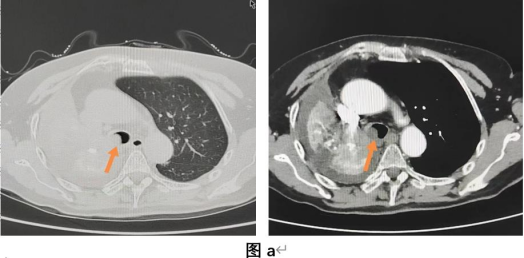

该患者为60岁男性,因咳嗽、胸闷3月,加重伴喘憋5天入院,既往诊断为肺恶性肿瘤(T2N1M1b,IVA期),入院后查胸部加强CT提示右肺占位、右主支气管阻塞(见图a),肺病一科在李平院长、闫平主任指导下通过集体讨论,考虑患者单肺呼吸、治疗风险高、麻醉风险较大,且右主支气管阻塞导致呼吸困难,常规治疗效果差,决定为患者在手术室全麻下行经支气管镜肿瘤切除术。术前主治医师严格进行术前评估,设计好各种应急预案,术中由张庆翔医师、张凯凯医师操作,李贵萍护士、杨敏护士协助,运用电圈套、氩气刀(APC)和冷冻技术,顺利完成经支气管镜肿瘤切除术,术后患者咳嗽、喘憋等症状明显缓解,无明显并发症及不良反应发生。

中央型气道肿瘤是指发生于气管、左右主支气管及右中间段支气管的肿瘤,其引起的气道狭窄可导致患者在临床上出现不同程度的呼吸困难甚至窒息死亡。过去主要是外科手术治疗,但外科手术创伤大、风险高、容易复发,有相当多的患者并不适合外科治疗且术后并发症亦不少见。当前经支气管镜介入治疗已逐渐成为处理中央气道肿瘤的主要手段。因其操作简单,更加安全、有效,创伤小、风险低,不易复发的优点,肺病一科运用高频电、氩气刀(APC)和冷冻技术成功为患者切除了支气管肿瘤(见图b)。术后患者右主支气管打通,右中下叶显露,患者喘憋症状明显缓解(见图c)。